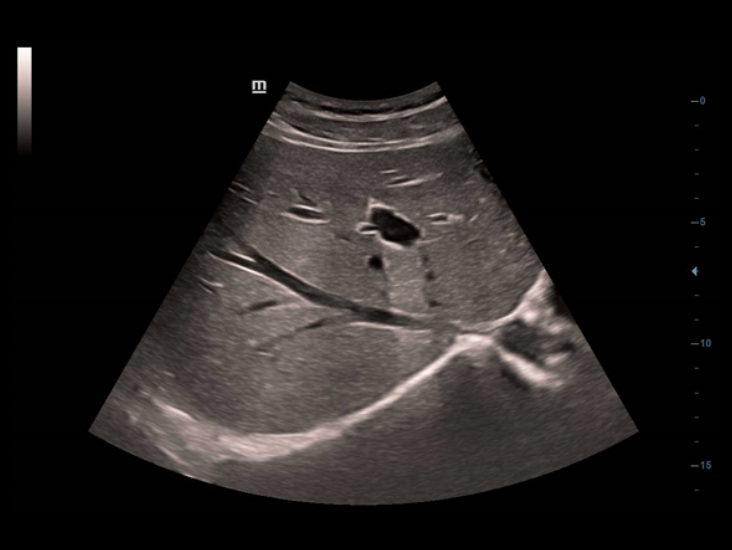

–†–Β―à–Β–Ϋ–Η–Β –¥–Μ―è ―É―Ä–Ψ–Μ–Ψ–≥–Η–Η

–Γ–Ω–Β―Ü–Η–Α–Μ―¨–Ϋ–Ψ ―Ä–Α–Ζ―Ä–Α–±–Ψ―²–Α–Ϋ–Ϋ―΄–Β –±–Η–Ω–Μ–Α–Ϋ–Ψ–≤―΄–Β –¥–Α―²―΅–Η–Κ–Η, –≤ ―²–Ψ–Φ ―΅–Η―¹–Μ–Β –Μ–Η–Ϋ–Β–Ι–Ϋ―΄–Β/–Κ–Ψ–Ϋ–≤–Β–Κ―¹–Ϋ―΄–Β –Η –¥–≤–Ψ–Ι–Ϋ―΄–Β –Φ–Η–Κ―Ä–Ψ–Κ–Ψ–Ϋ–≤–Β–Κ―¹–Ϋ―΄–Β, –Ψ–±–Β―¹–Ω–Β―΅–Η–≤–Α―é―² ―É–Ϋ–Η–≤–Β―Ä―¹–Α–Μ―¨–Ϋ–Ψ–Β ―É―Ä–Ψ–Μ–Ψ–≥–Η―΅–Β―¹–Κ–Ψ–Β ―Ä–Β―à–Β–Ϋ–Η–Β –¥–Μ―è ―Ä–Α―¹―à–Η―Ä–Β–Ϋ–Η―è –£–Α―à–Η―Ö –≤–Ψ–Ζ–Φ–Ψ–Ε–Ϋ–Ψ―¹―²–Β–Ι.

DC-40 ―¹ Full HD –Ω–Ψ–¥–¥–Β―Ä–Ε–Η–≤–Α–Β―² ―à–Η―Ä–Ψ–Κ–Η–Ι –¥–Η–Α–Ω–Α–Ζ–Ψ–Ϋ –Η–Ϋ―¹―²―Ä―É–Φ–Β–Ϋ―²–Ψ–≤, –Κ–Ψ―²–Ψ―Ä―΄–Β –Ψ–±–Β―¹–Ω–Β―΅–Η–≤–Α―é―² –Φ–Α–Κ―¹–Η–Φ–Α–Μ―¨–Ϋ―É―é ―²–Ψ―΅–Ϋ–Ψ―¹―²―¨ –¥–Η–Α–≥–Ϋ–Ψ―¹―²–Η–Κ–Η –Η ―É–¥–Ψ–±―¹―²–≤–Ψ. –Γ–Η―¹―²–Β–Φ–Α DC-40 ―¹ Full HD, –Ψ―Ö–≤–Α―²―΄–≤–Α―é―â–Α―è –Ψ–±―à–Η―Ä–Ϋ―΄–Ι –¥–Η–Α–Ω–Α–Ζ–Ψ–Ϋ –Ψ–±–Μ–Α―¹―²–Β–Ι –Ω―Ä–Η–Φ–Β–Ϋ–Β–Ϋ–Η―è: –Ψ–±―â―É―é –≤–Η–Ζ―É–Α–Μ–Η–Ζ–Α―Ü–Η―é, –Α–Κ―É―à–Β―Ä―¹―²–≤–Ψ, –≥–Η–Ϋ–Β–Κ–Ψ–Μ–Ψ–≥–Η―é –Η –Κ–Α―Ä–¥–Η–Ψ–Μ–Ψ–≥–Η―é, –Ω―Ä–Β–¥–Ψ―¹―²–Α–≤–Μ―è–Β―² –Κ–Ψ–Φ–Ω–Μ–Β–Κ―¹–Ϋ―΄–Β ―Ä–Β―à–Β–Ϋ–Η―è –¥–Μ―è –Ψ―¹–Ϋ–Ψ–≤–Ϋ―΄―Ö –Κ–Μ–Η–Ϋ–Η―΅–Β―¹–Κ–Η―Ö –Ζ–Α–¥–Α―΅ ―¹ ―É–Ω―Ä–Ψ―â–Β–Ϋ–Ϋ―΄–Φ ―Ä–Α–±–Ψ―΅–Η–Φ –Ω―Ä–Ψ―Ü–Β―¹―¹–Ψ–Φ, –Ω–Ψ–≤―΄―à–Α―é―â–Η–Φ –Ω―Ä–Ψ–Η–Ζ–≤–Ψ–¥–Η―²–Β–Μ―¨–Ϋ–Ψ―¹―²―¨.